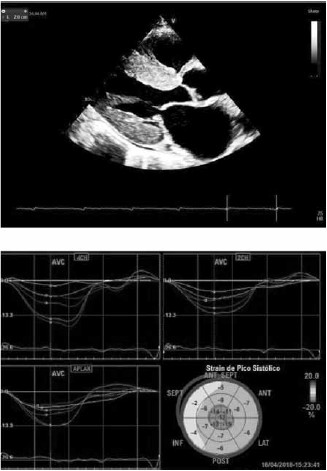

Homem, 75 anos, apresenta dispneia aos esforços e ortopneia. Antecedentes pessoais: hipertensão arterial, síndrome do túnel do carpo e litíase renal. O ecocardiograma mostra as imagens a seguir:

(Arquivo pessoal; imagens usadas com autorização)

Assinale a alternativa correta quanto à hipótese diagnóstica.